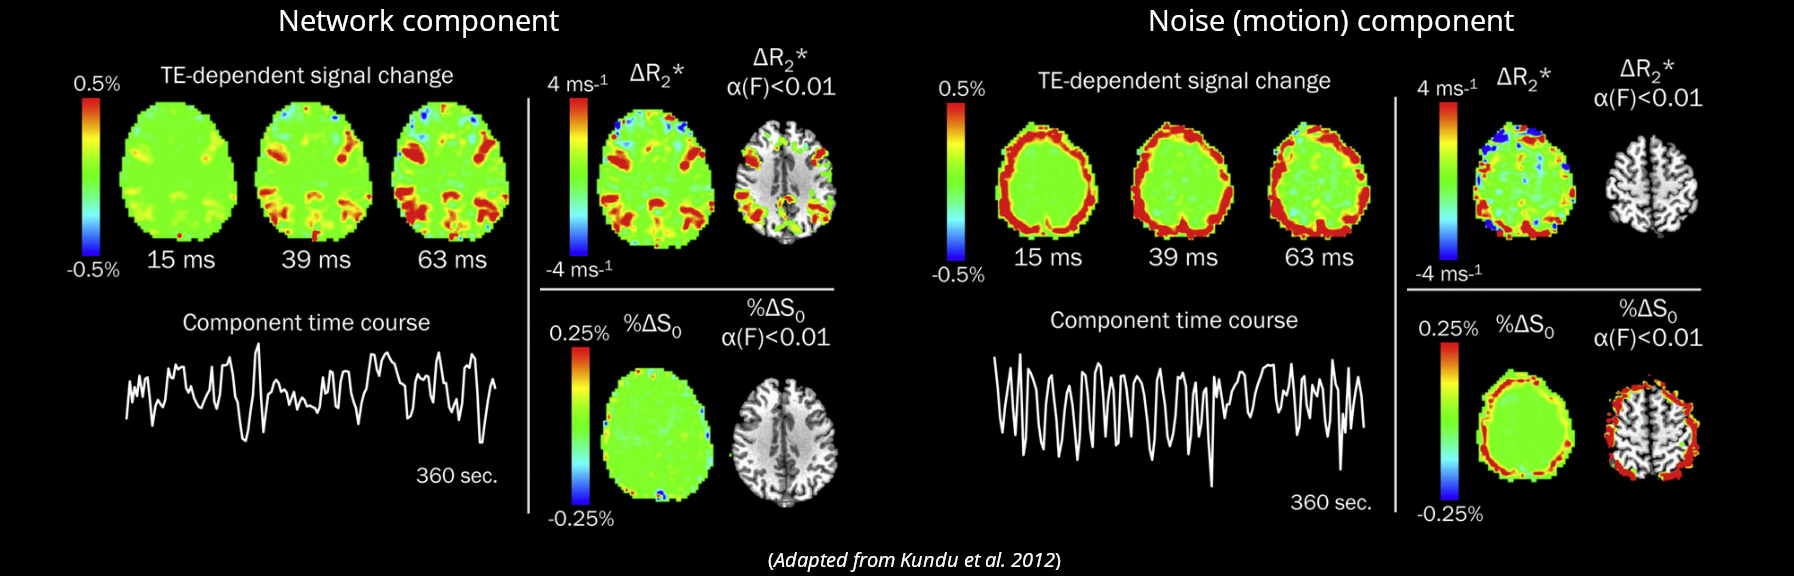

ME-ICA

Assuming monoexponential decay, we can express the

signal percentage change as:

\[ S_{SPC} \approx \Delta\rho - TE \cdot \Delta R_2^{\star} + n \quad where \enspace R_2^{\star} = \frac{1}{T_2^{\star}} \]

This let us differentiate BOLD-related (\(\Delta R_2^{\star}\)) from non-BOLD related (\(\Delta\rho\)) changes

Kundu et al. 2012 (NeuroImage)

If we apply ICA, we can fit the timeseries of the components to either sub-models and automatically classify them